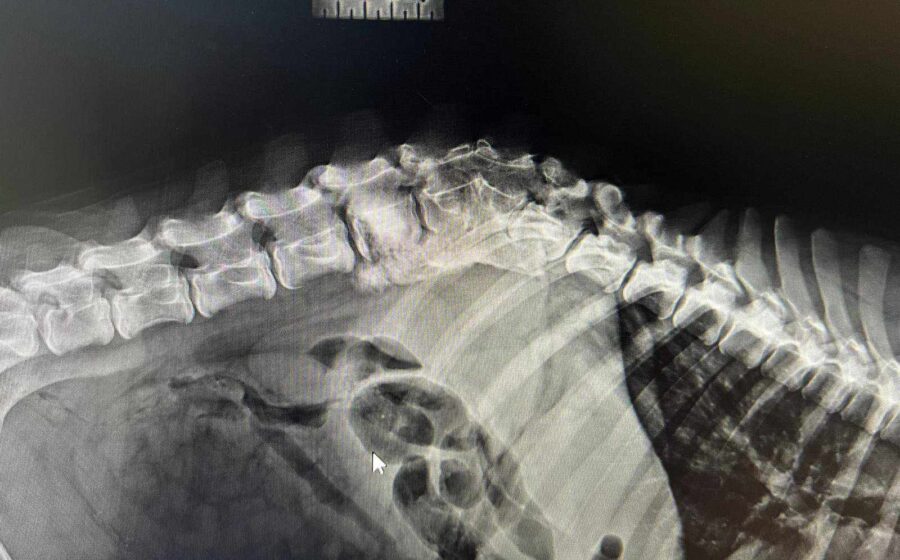

Sommersprosse stand seit seiner Geburt wacklig auf seinen Hinterbeinen. Sein 92-jähriger Besitzer, der Sommersprosse ausschließlich im Haus hielt, weigerte sich jedoch, den Welpen untersuchen zu lassen. Um die Wachstumsentwicklung von Sommersprosse zu unterstützen, ging unsere Tierschützerin Tina regelmäßig vorbei und brachte Futter, Vitamine, Mineralien und Ergänzungsmittel mit. Eines Tages beschloss der alte Mann, Sommersprosse nach draußen zu lassen, wo er prompt von einem Auto angefahren wurde. Daraufhin hat Tina Sommersprosse zu sich in Pflege genommen und ihn direkt untersuchen lassen. Auf den Röntgenbildern wurden angeborene Schäden der Wirbelsäule und Hinterläufe, sowie ein weiterer Wirbelsäulenschaden durch den Unfall festgestellt. Spazierte Sommersprosse anfangs noch auf wackligen Hinterbeinen durchs Leben, hat sich seine Gehbehinderung jetzt deutlich verschlechtert. Auch ist der süße Bub hierdurch größtenteils inkontinent geworden und braucht spezielle Versorgung.

Das bedeutet, dass seine Blase manuell entleert werden muss.